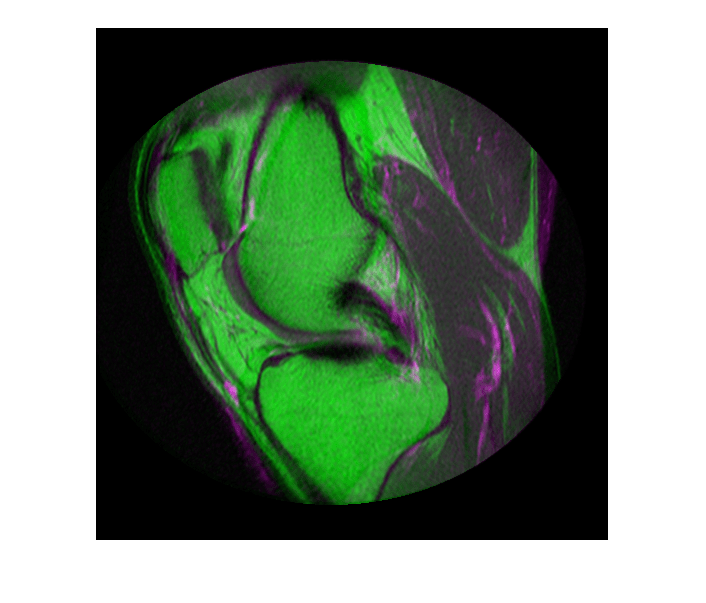

Считайте два изображения. Этот пример использует два магнитных резонанса (MRI) изображения колена. Фиксированное изображение является двойным изображением вращения, в то время как движущееся изображение является двойным изображением вращения с восстановлением инверсии. Два стреловидных среза были получены одновременно, но немного неровно.

Просмотрите неправильно выровненные изображения.

imshowpair(fixed, moving,'Scaling','joint')

Просмотрите зарегистрированные изображения.

figure

imshowpair(fixed, movingRegistered,'Scaling','joint')